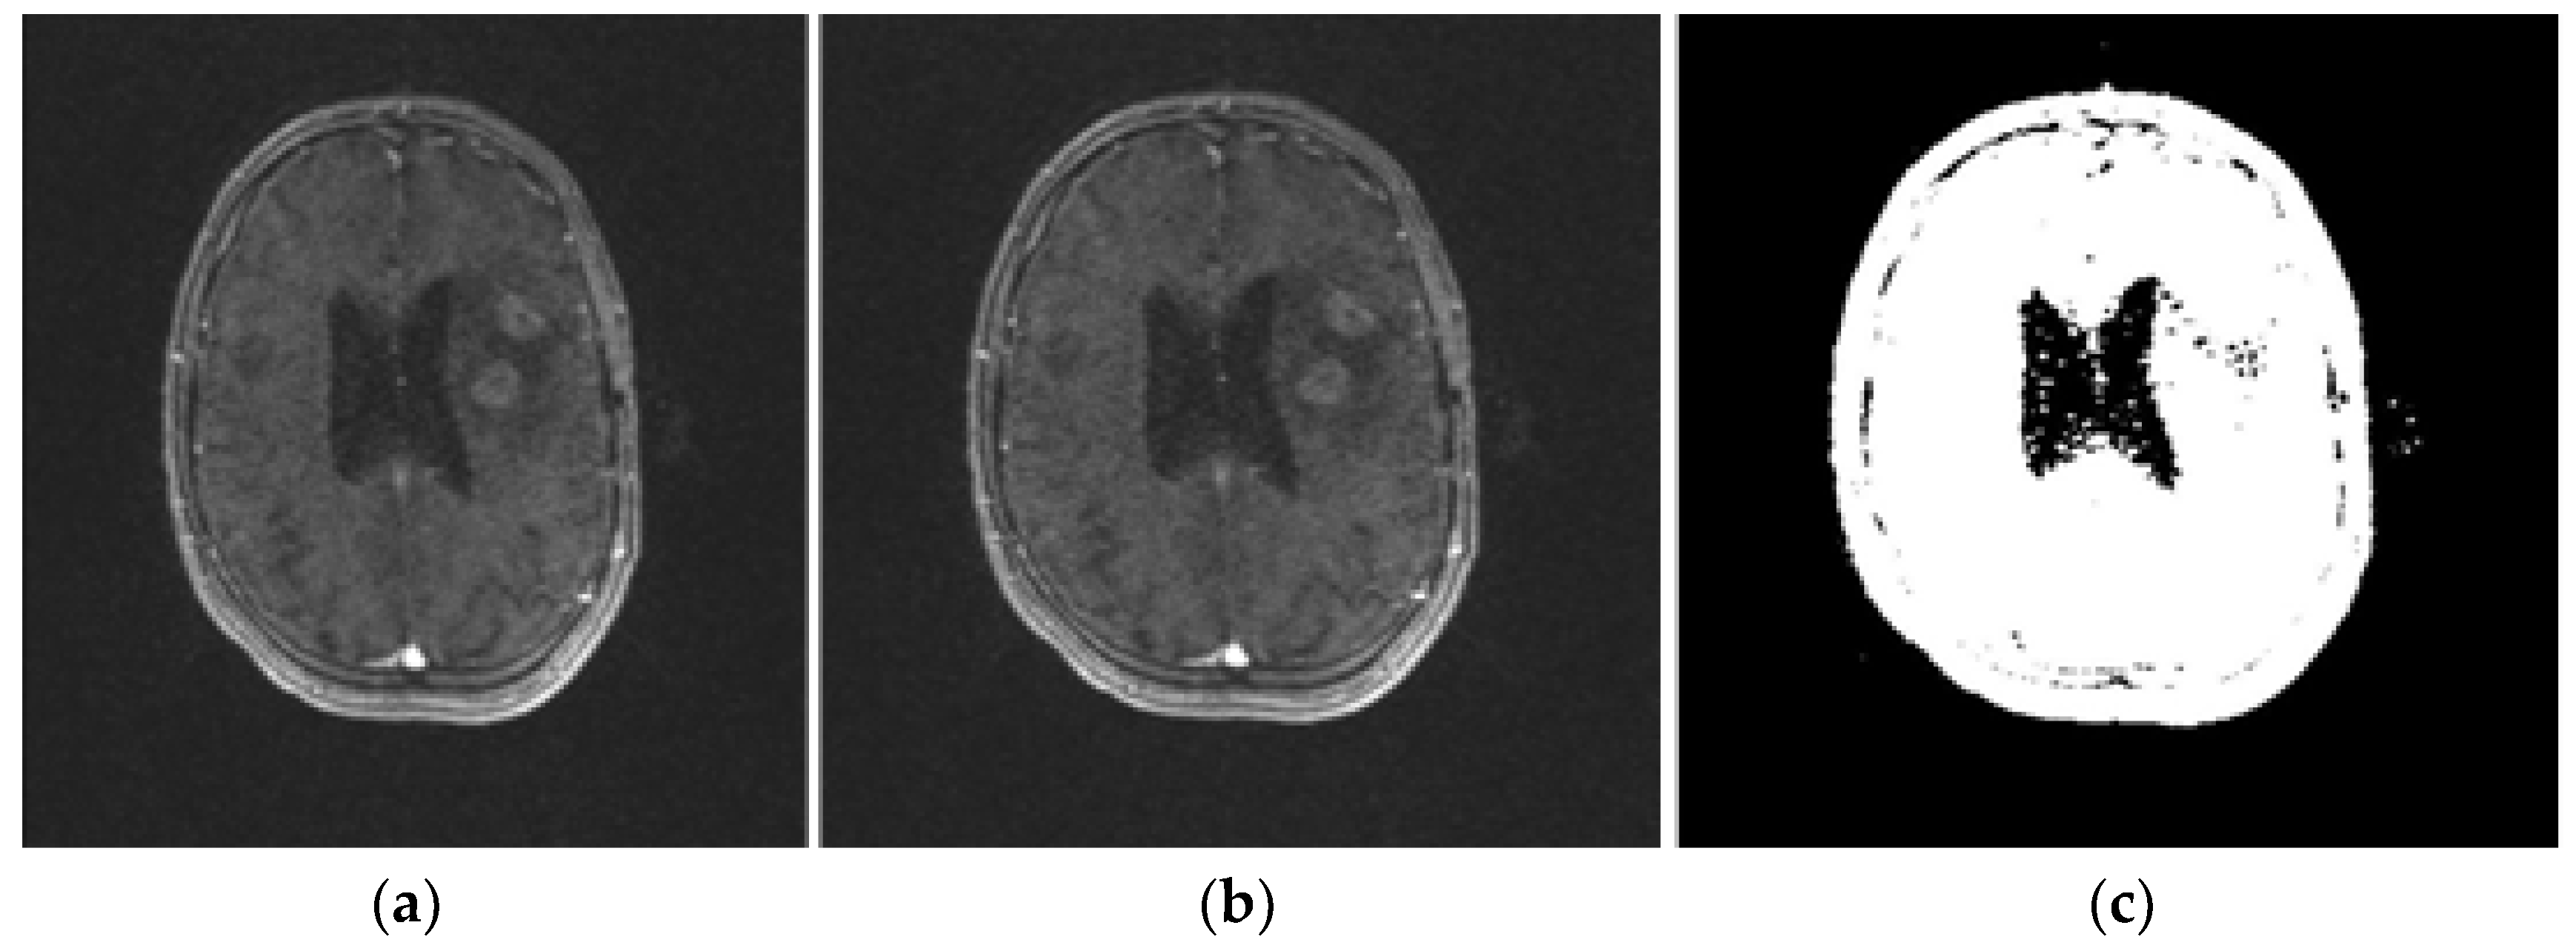

2.2.1. Input Human Brain MR Images

2.2.2. Bitmap Conversion

2.2.3. Noise Removal

2.2.4. Grayscale Conversion

2.2.5. Image Enhancement

2.2.6. Image Binarization

2.2.7. Area Segmentation using Watershed Algorithm